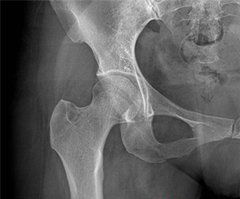

大腿刺痛2.CT檢查。可較清楚地顯示椎間盤突出的部位、大小、形態和神經根、硬脊膜囊受壓移位的情況,同時可顯示椎板及黃韌帶肥厚、小關節增生肥大、椎管及側隱窩狹窄等情況,對本病有較大的診斷價值,目前已普遍採用。

應與引起大腿外側痛的股外側皮神經炎和股外側皮神經卡壓綜合徵相鑑別。

1.股外側皮神經炎。又稱感覺異常性股痛,股外側皮神經系由第2~3腰神經發出,通過腰大肌外側緣,斜過髂肌,沿骨盆經腹股溝韌帶之深面,在髂前上棘以下10厘米處穿出闊筋膜至股部皮膚。在該神經行程中,如果由於受壓、外傷等某種原因影響到股外側皮神經時,即可能發生股外側皮神經炎。多見於較肥胖的中青年男性。

2.股外側皮神經卡壓綜合徵。是該神經在途經之處因某種致壓因素卡壓而引起的神經功能障礙。